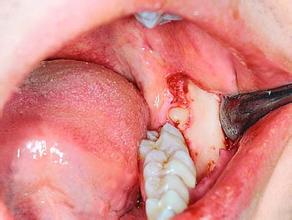

需要拔牙的情况还是很多的,像常见的阻生智齿需要拔掉,没有继续留存意义的坏牙根要拔掉,有时候在做牙齿矫正的时候为了更好的矫正牙齿也是要拔牙处理,那拔牙贵不贵呢?拔牙价格是怎样的呢?

优先,与所要拔牙的位置有关。拔牙的位置不同,那拔牙的价格就不一样,一般前牙拔牙费用较低,而后牙拔牙的费用就高,特别是智齿,是所有拔牙价格中高的一种。